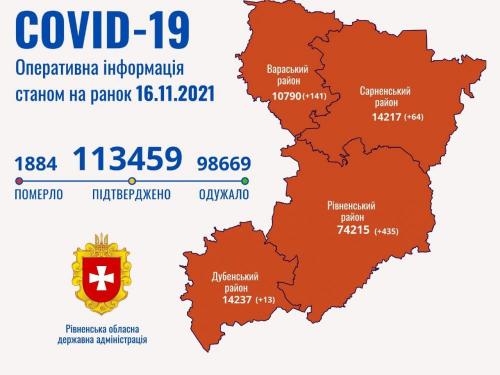

Депутати Вараської міської ради виділили майже 2 мільйони для придбання тест-систем

19.11.2021 11:08